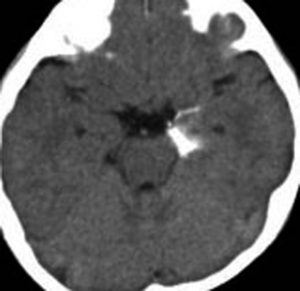

第4室床過誤腫の典型例です

新生児期より動作停止と右眼瞼のちく搦,4ヶ月で右眼の閉眼と口角の引きつれ(顔面けいれん)が目立つようになりました。2歳時には数十秒ごとに発作を繰り返していました。

MRIでは橋の背側(第4脳室床)にT1/T2で等信号の隆起(腫瘤)がみられました。